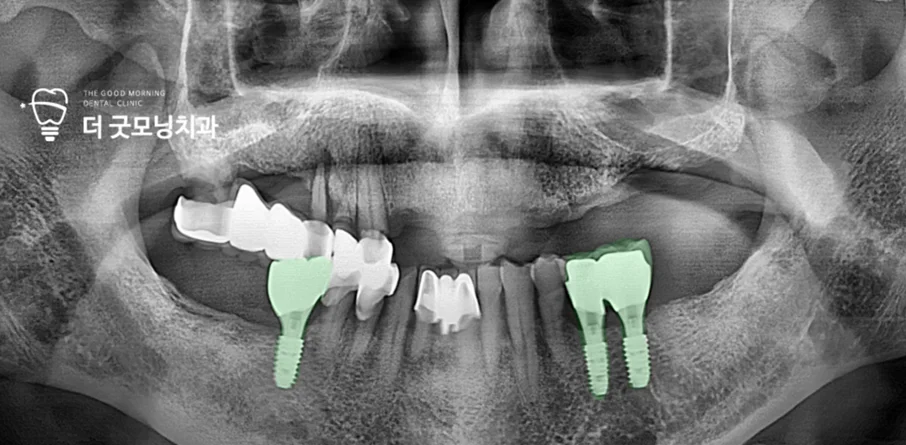

Step 2. 하악 치료 — 국민건강보험 임플란트 적용

해당 환자는 70대였으며, 잔존치가 있었기 때문에 국민건강보험 임플란트 혜택을 받을 수 있었습니다. 충치로 보존이 어렵던 하악 어금니 2개를 발치한 후, 건강보험 임플란트 2개와 비급여 임플란트 1개를 식립하여 하악 치료를 완료했습니다.